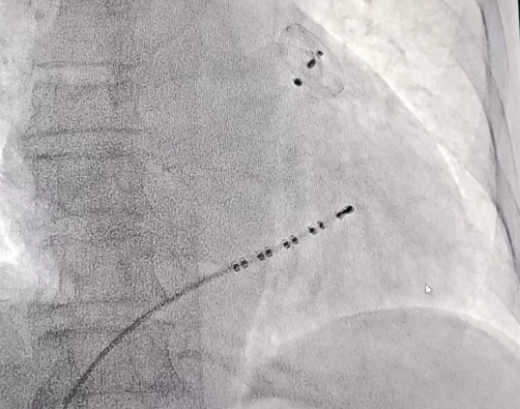

图片

术中影像片